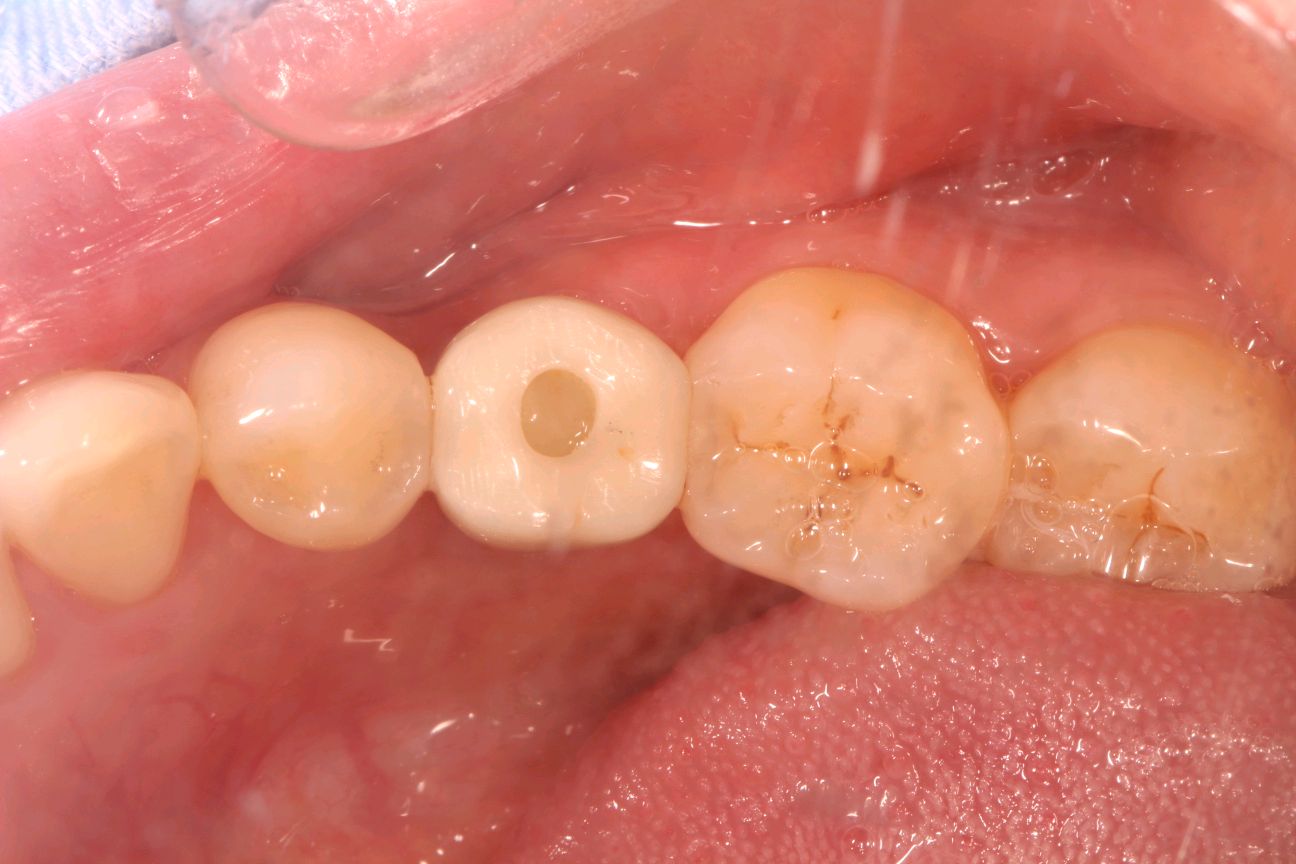

患者女三十岁,35畸形中央尖折断,根尖周炎症感染,导致牙根发育停止,根尖口呈喇叭口状。拔出后搔刮牙槽窝,颊侧骨壁吸收,植入骨粉骨膜。定期复查,将近半年见骨密度良好,骨量充足的条件下,行种植手术。植入3I 4/3*11.5mm的种植体。二期三期如期进行,与今日戴牙,患者满意。

术后